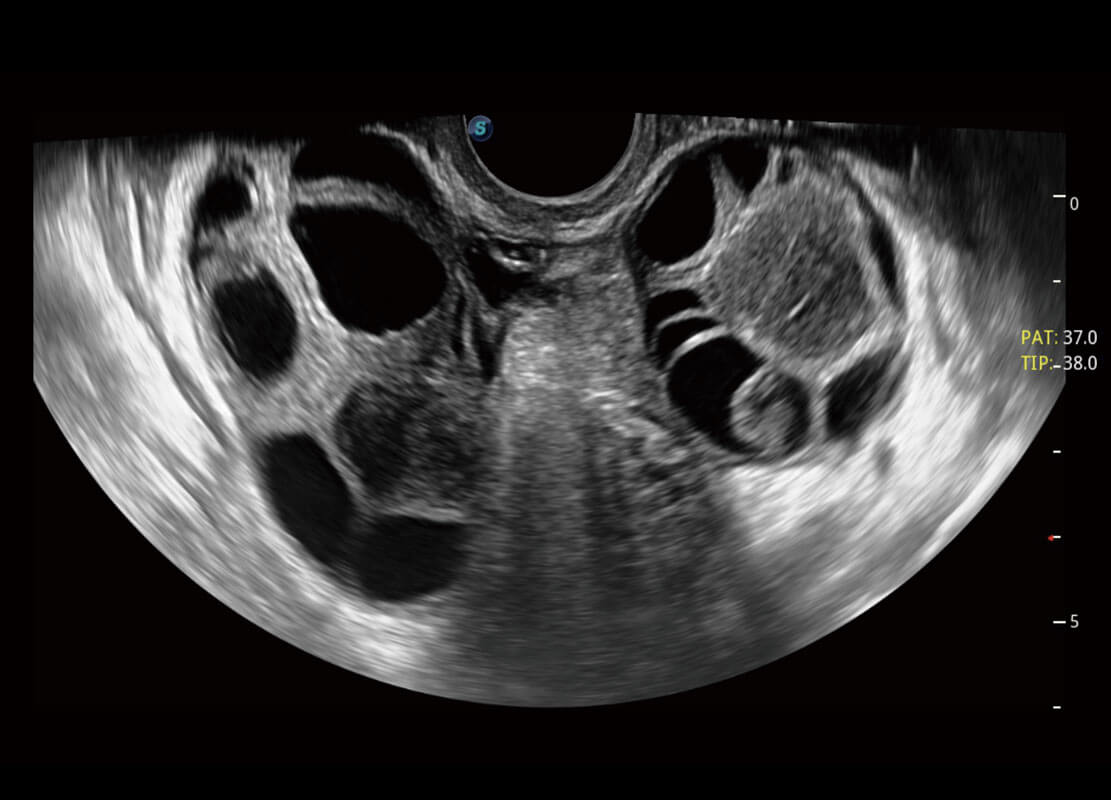

盆底超声

P60为盆底超声检查提供应用方案,多种腔内及腹部容积探头提供从二维、三维到四维的优异图像品质,实时快速三维容积数据获取,专业的测量工具包等人性化设计,为超声医生诊断提供有力保障。